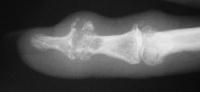

Clinical Example: Distal Interphalangeal Joint Arthroplasty with reversed Ascension carbon implant arthroplasty

These two cases illustrate the use of the Ascension PIP joint implant arthroplasty in the DIP joint position. The stem of the distal component is too wide to fit into the typical distal phalanx, but the proximal component stem will, and in selected cases, the implant will fit in this position if it is placed in a reversed proximal-distal position. These cases illustrate this technique - not as an endorsement, but as a demonstration of  technical feasibility. At one year, each  reconstructed joint was painless and had about 30 degrees range of motion.

Distal interphalangeal erosive osteoarthritis severe enough that the diagnosis of giant cell or other tumor was suspected. Fortunately, no tumor was encountered at surgery.